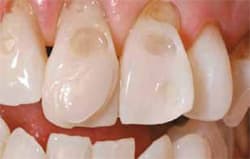

- Severe erosion of the anterior dentition was present upon clinical examination, extending past the enamel into the dentin.

| Preoperative smile view of the patient. | Preoperative view of the patient.(View Figure) | ||||||

| Note extent of patient’s cavities.(View Figure) | Note extent of patient’s cavities.(View Figure) | ||||||